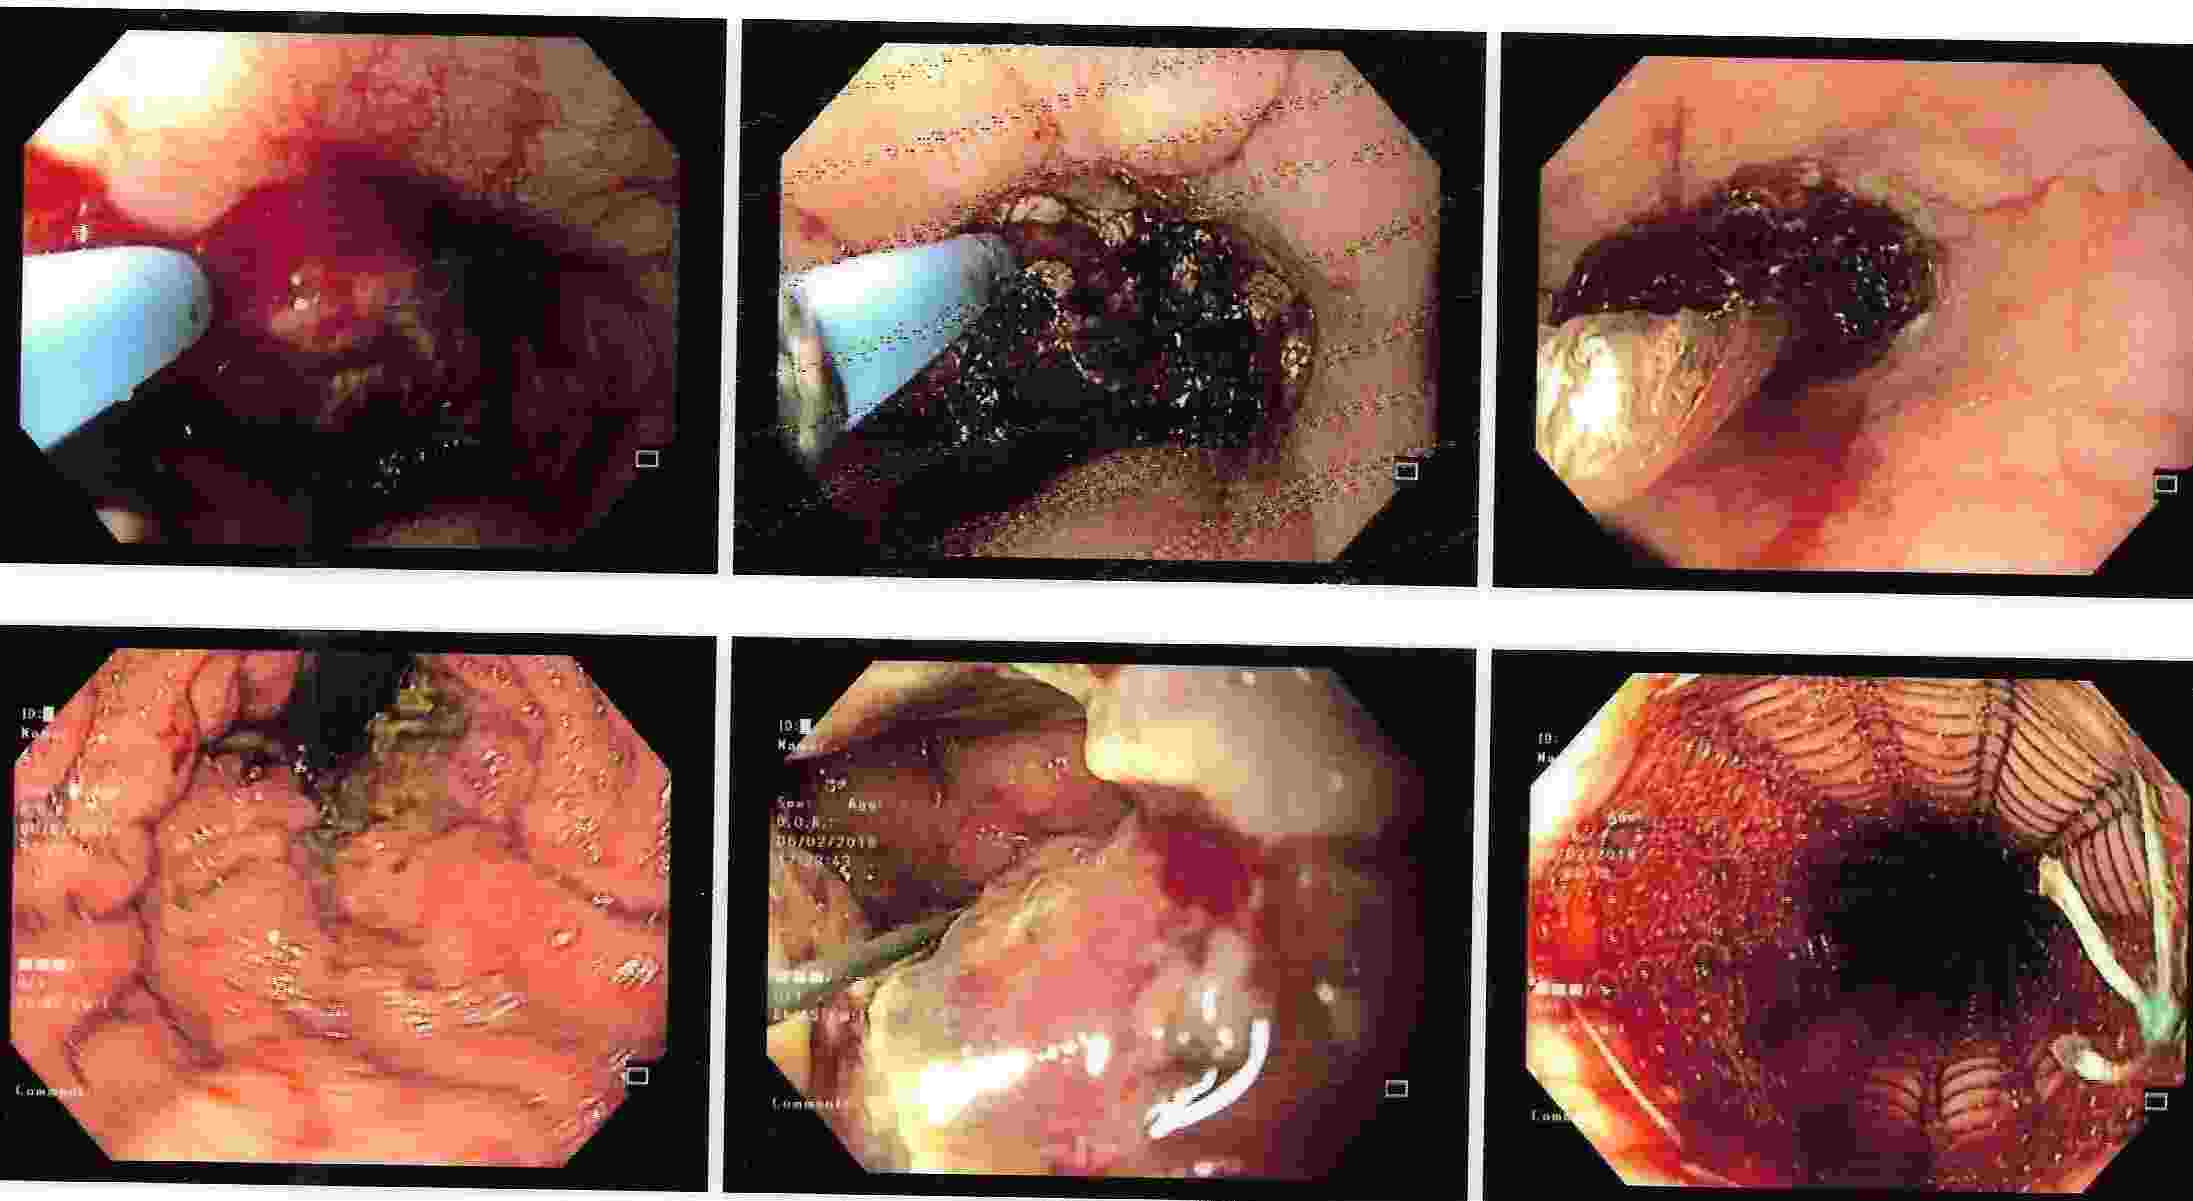

Vomiting of Blood - Endoscopic Treatment

Cirrhosis of Liver - Bleeding from Gastric Varices

A jet like bleeding from gastric varices can be life threatening and is effectively controlled by endoscopic therapy.

Stomach Outlet Obstruction

Causing Abdominal Fullness and Vomiting

Cancer of the Stomach with Vomiting

Tumours of the Stomach

Polyps of the Stomach